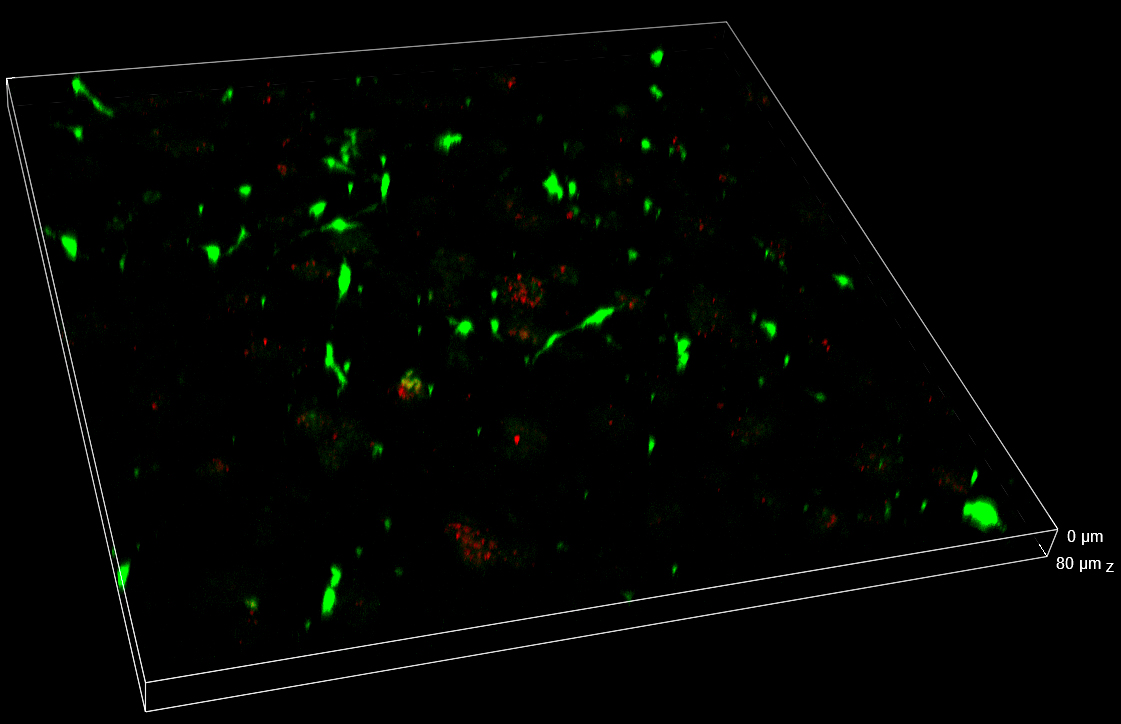

In the Figure 2, the full field of view (FOV) in XYZ dimensions collected 24 h post-treatment is shown. Thanks to the 25 mm diagonal FOV of the camera and to the ability to penetrate inside the sample without losing the spinning disk confocality, it was possible to visualize and record cells that homogeneously colonize the entire thickness of the 3D matrix.

Figure 2. 3D view of the entire FOV acquired with spinning disk at 24 h post-treatment. FOV with XY=4422×4422 µm, Z=530 µm. 3D matrix thickness was entirely acquired. Tumor target A673 cells are shown in red and AD-MSCs TRAIL in green.